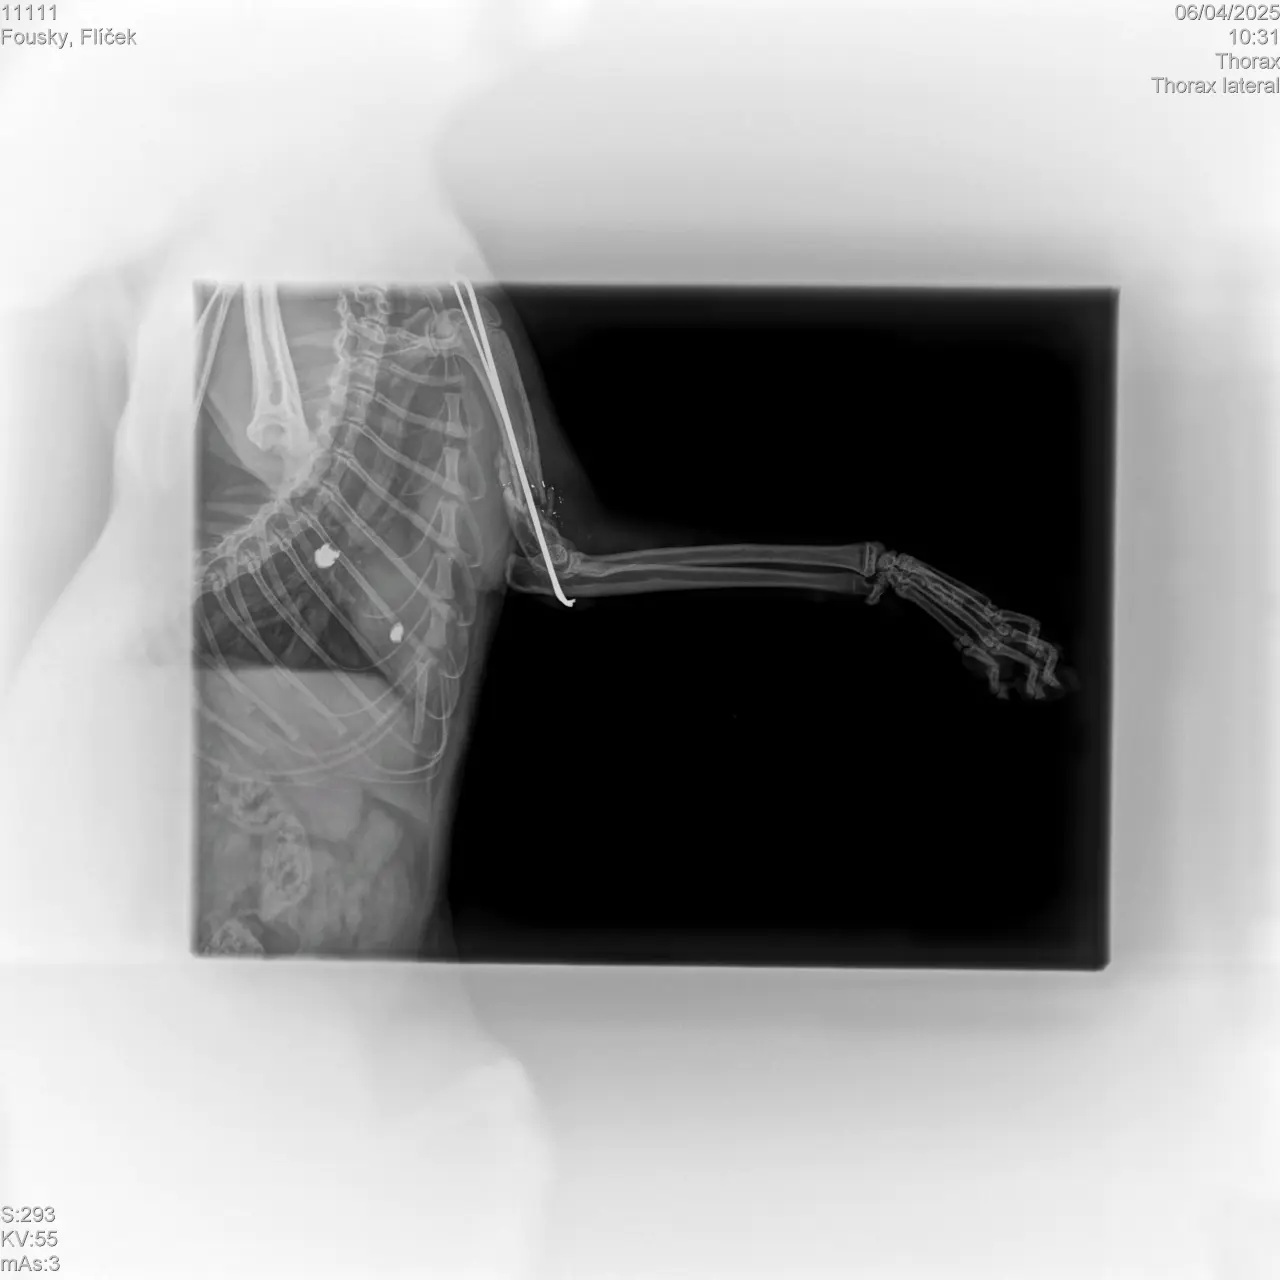

Díky Vašim darům jsme mohli pro Flíčka zajistit špičkovou péči a operaci, která mu zachránila nožičku. A nebyla to obyčejná operace. Na pana doktora čekala dvě velká překvapení: poškozený loketní kloub od původního pinu a nerv vrostlý mezi dva kostní úlomky, které ho doslova obrůstaly. I přes veškerou snahu nešlo nerv uvolnit. Ale pan doktor udělal maximum. ❤️ Uvidíme, zda to do budoucna bude nebo nebude Flíčkovi způsobovat potíže nebo bolesti.

Flíček je každopádně teď tak trochu Terminátor. V pacince má hned dvě titanové destičky, vytažený velký úlomek kosti páni doktoři rozemleli a vrátili zpět, díky čemuž mohla kost lépe dorůst… Hojení bude dlouhé, říkal pan doktor. Ale výsledek? Flíček běhá, skáče, mazlí se, hraje si a hlavně – už ho NIC nebolí. 🐾😻

Bohužel, i když měl Flíček velkou kliku a přitoulal se k lidem, kterým nebyl osud toulavého kocourka lhostejný, zákrok se nepovedl. Drát, který měl kost stabilizovat, nefunguje. Kost se dále tříští, a tak místo pomoci Flíčkovi způsobuje bolest, zánět a hrozí, že o pacičku přijde úplně. 🥺 Dnes má Flíček jedinou šanci – náročnou reoperaci na specializované klinice, která by mu mohla zachránit nožičku a umožnit mu běhat po všech čtyřech. Operace je však drahá a s ní i potřebná následná péče, léky, hospitalizace, případně rehabilitace.